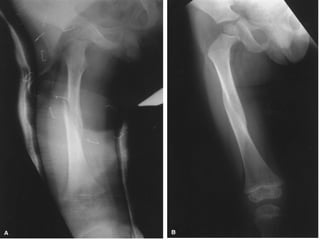

RELACION DE LOS FRAGMENTOS ENTRE SI Sin desplazamiento Con desplazamiento: lateral, angulada, rotación, diastasado, cabalgado, impactada

RELACION DE LOSFRAGMENTOS ENTRE SI Sin desplazamiento Con desplazamiento: lateral, angulada, rotación, diastasado, cabalgado, impactada